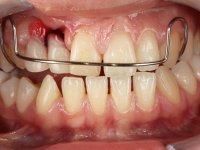

Female patient, 20 years old, non-smoker, had several surgical interventions to correct labial and palatal cleft. Patient presented a significant edentulous area between teeth 13 and 11, also due to the absence of teeth 12 and 15. Due to a traumatic impact, tooth 11 was non-vital, and extensively reconstructed with composite. Patient also had an orthodontic appliance with two prosthetic teeth and a buccal arch in this area to avoid teeth movement in this area. The area of the surgical correction of the labial and palatal cleft presented a significant deformity of hard and soft-tissues.